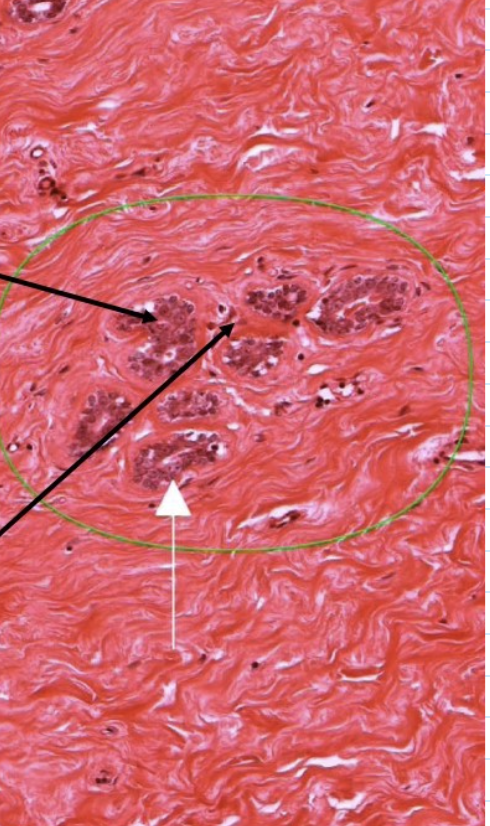

what is this slide

top = stratum functionale

bottom = stratum basale

endometrium of uterus